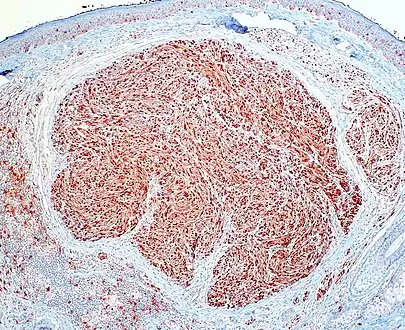

PEN is diagnosed by clinical recognition of the lesion and on subsequent histologic examination. Typically, the lesions are suspected to be schwannomas or neurofibromas clinically with PEN being an incidental finding on histology.[3]

PEN is typically diagnosed in patients between the ages of 40 and 60 years and occurs more frequently in females than males. The diagnosis of PEN may be difficult, even with confirmatory histology, due to its histological similarities with schwannomas and neurofibromas. It is imperative that the correct diagnosis is made the misdiagnosis of a neurofibroma may lead to unnecessary further investigation into associated systemic syndromes such as neurofibromatosis type 1 or multiple endocrine neoplasia syndrome.[3][4]

Skin tumors(palisaded encapsulated neuroma)